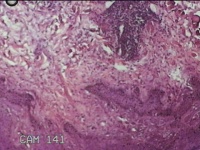

左侧腰部皮肤息肉组织

性别

男

年龄

40岁

临床诊断

皮肤和皮下组织良性脂肪瘤样肿瘤,其他部位的

一般病史

发现左侧腰部皮肤息肉组织5年余。

标本名称

大体所见

灰白暗红色息肉样组织1.7x1.3x0.3cm一块,表面糜烂,切面灰白暗红色,质软。